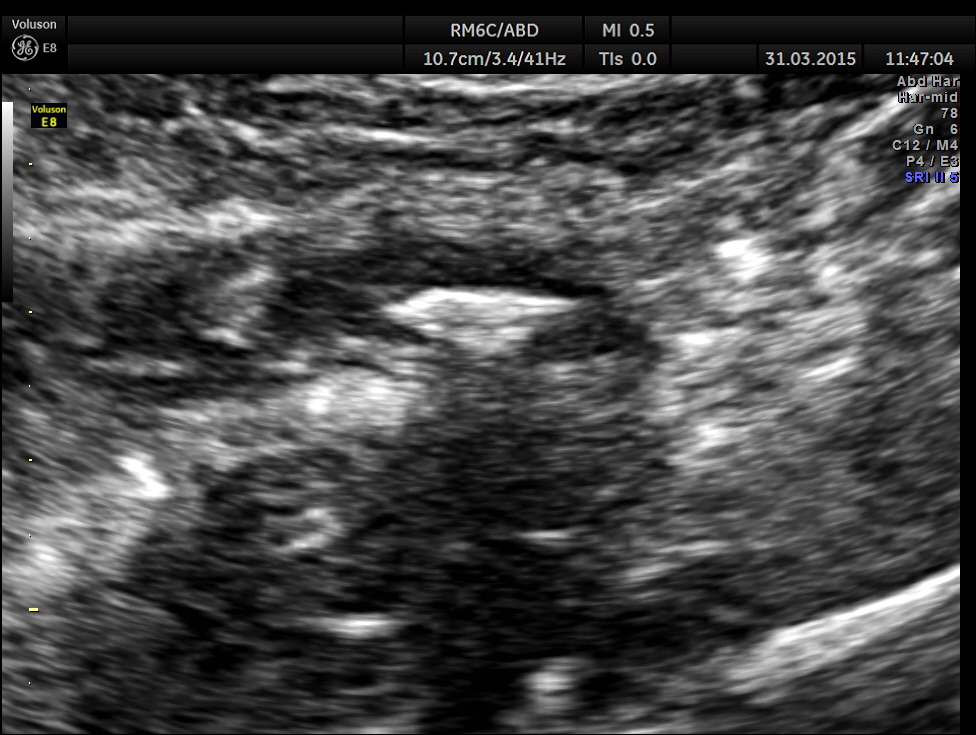

The following pictures are with a high resolution probe.

The following picture shows the long and short axis views.

Careful attempt to establish any continuity of the dilated ” tube ” to the ureter or dilated pelvis , showed that the dilated structure was separate from the right ureter .